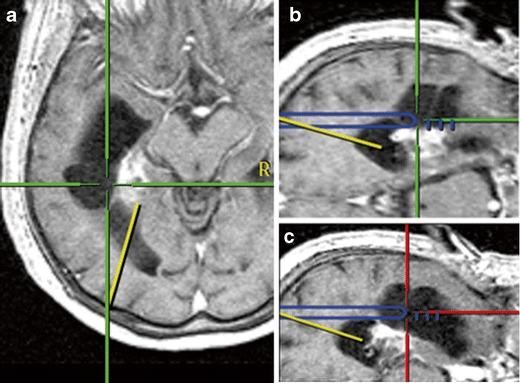

In occlusive hydrocephalus, cysts and some ventricular tumours, neuroendoscopy has replaced shunt operations and microsurgery. There is an ongoing discussion if neuronavigation should routinely accompany neuroendoscopy or if its use should be limited to selected cases. In this prospective clinical series, the role of neuronavigation during intracranial endoscopic procedures was investigated. In 126 consecutive endoscopic procedures (endoscopic third ventriculostomy, ETV, n = 65; tumour biopsy/resection, n = 36; non-tumourous cyst fenestration, n = 23; abscess aspiration and hematoma removal, n = 1 each), performed in 121 patients, neuronavigation was made available. After operation and videotape review, the surgeon had to categorize the role of neuronavigation: not beneficial; beneficial, but not essential; essential. Overall, neuronavigation was of value in more than 50% of the operations, but its value depended on the type of the procedure. Neuronavigation was beneficial, but not essential in 16 ETVs (24.6%), 19 tumour biopsies/resections (52.7%) and 14 cyst fenestrations (60.9%). Neuronavigation was essential in 1 ETV (2%), 11 tumour biopsies/resections (30.6%) and 8 cyst fenestrations (34.8%). Neuronavigation was not needed/not used in 48 ETVs (73.9%), 6 endoscopic tumour operations (16.7%) and 1 cyst fenestration (4.3%). For ETV, neuronavigation mostly is not required. In the majority of the remaining endoscopic procedures, however, neuronavigation is at least beneficial. This finding suggests integrating neuronavigation into the operative routine in endoscopic tumour operations and cyst fenestrations.

在闭塞性脑积水、囊肿和一些脑室肿瘤中,神经内镜已取代分流手术和显微镜手术。目前正在讨论神经导航是否应常规用于神经内镜检查,还是应将其使用限于某些特定病例。在这项前瞻性临床系列研究中,研究了神经导航在颅内内镜手术中的作用。在 121 名患者中进行的 126 例连续内镜手术(内镜第三脑室造瘘术,ETV,n=65;肿瘤活检/切除术,n=36;非肿瘤性囊肿开窗术,n=23;脓肿抽吸和血肿清除术,各 1 例)中,提供了神经导航。手术后和录像带审查后,外科医生必须对神经导航的作用进行分类:无益处;有益但并非必不可少;必不可少。总的来说,神经导航在超过 50%的手术中具有价值,但它的价值取决于手术类型。神经导航在 16 例 ETV(24.6%)、19 例肿瘤活检/切除术(52.7%)和 14 例囊肿开窗术(60.9%)中有益但并非必不可少。神经导航在 1 例 ETV(2%)、11 例肿瘤活检/切除术(30.6%)和 8 例囊肿开窗术(34.8%)中是必不可少的。神经导航在 48 例 ETV(73.9%)、6 例内镜肿瘤手术(16.7%)和 1 例囊肿开窗术(4.3%)中不需要/未使用。对于 ETV,神经导航大多不需要。然而,在大多数其余的内镜手术中,神经导航至少是有益的。这一发现表明,在内镜肿瘤手术和囊肿开窗术中,应将神经导航纳入手术常规。